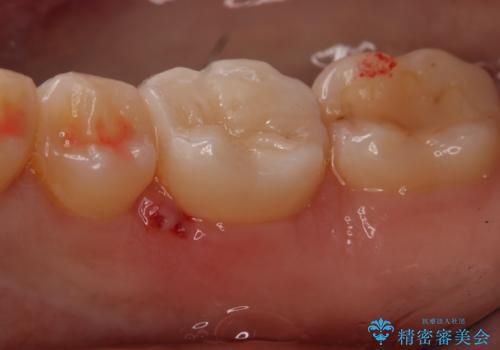

- 右下奥歯の虫歯治療を希望された患者様です。

保険の材料が劣化し、直下で虫歯の存在が確認出来ました。

セラミックを希望されたので形態・切削量を考慮し、セラミックインレーでの治療を計画しました。

虫歯が広く進行していましたが神経には到達していなかったので、予定通りセラミックインレーでの治療を行いました。